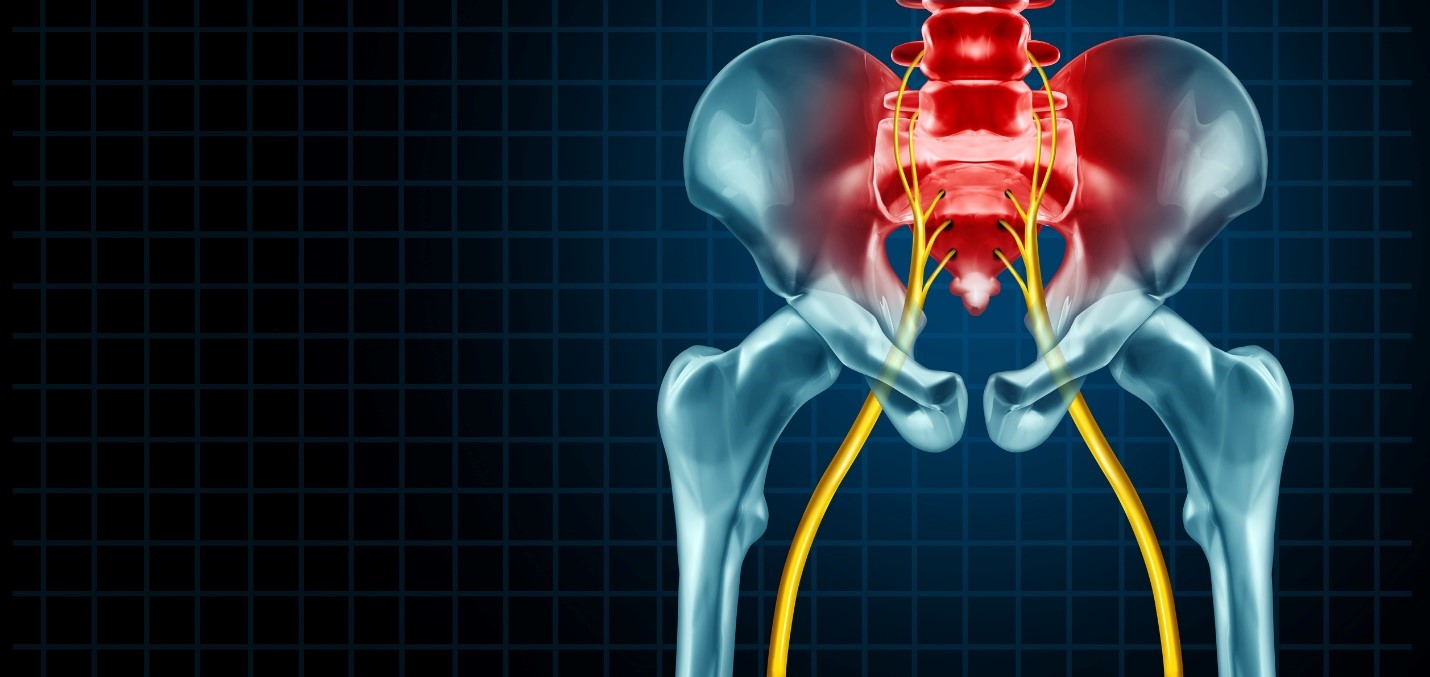

Where you have pain is where the problem ended up, NOT where it is coming from.